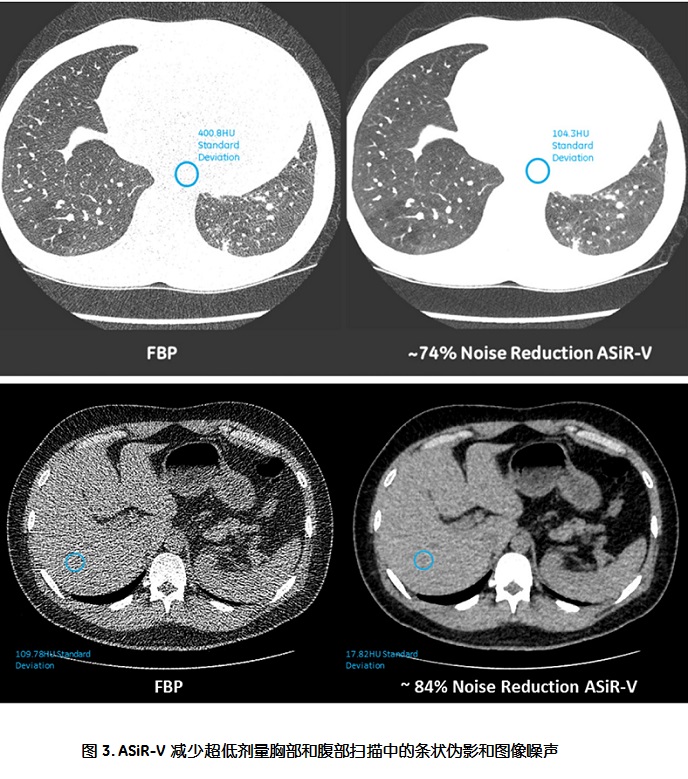

利用国际医学成像和技术协会和美国食品药品管理局所推荐的MITA-FDA CT IQ体模对ASiR-V的性能进行测试,结果显示对比FBP,ASiR-V可以降低多达82% 的辐射剂量。另一项实验显示,在相同的剂量条件下,与FBP相比,ASiR-V可以对低对比分辨率(LCD)提高135%。在临床实验中,ASiR-V同样可以显著地降低胸部图像和腹部的图像噪声(图3)。